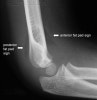

Elbow X-ray의 Fat pad sign

- Lateral view

1) Anterior & Posterior fat pad sign

Anterior fat pad is located in the coronoid fossa. A narrow anterior fat pad is a normal finding on the lateral view.

The posterior fat pad is located in the olecranon fossa on the lateral view. It should not be visible under normal circumstances.

Anterior fat pad sign : 70-80% Intra-articular fracture

Posterior fat pad sign : 90% Intra-articular fracture.

- Sail sign

The anterior fat pad can be displaced up and out by fluid in the elbow joint, creating the "sail sign". This usually indicates a fracture in children in the setting of an injury.

Fluid in the elbow joint can displace the fat pad up and out making it visible on the lateral view.

Indicates that the patient has sustained an intra-articular injury. Importantly, it does not indicate that the patient has definitely sustained an intra-articular bony injury.